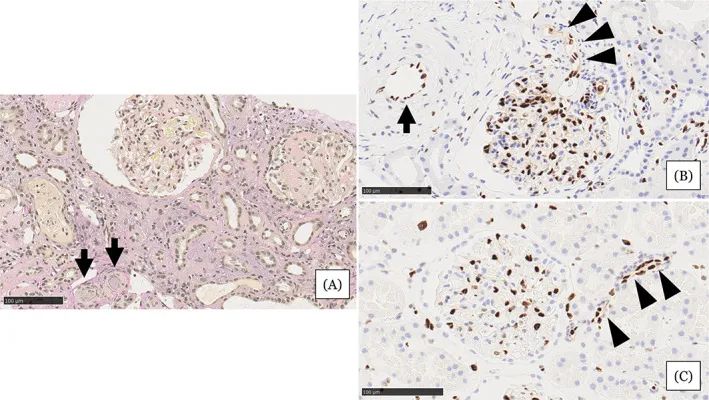

圖注:在住院第31天進行的腎活檢結(jié)果。A,顯示小動脈被粘液性內(nèi)膜增厚(箭頭)堵塞,腎小球萎縮,毛細血管壁起皺,嚴(yán)重的間質(zhì)單核細胞浸潤伴腎小管損傷。B,EC細胞核的缺乏在小動脈(箭頭)中很突出。在相鄰的小動脈(箭頭)中注意到不同大小的不規(guī)則細胞核。C,EC的等距核在血壓正常的腎臟供體的腎臟小動脈中形成有序的線。比例尺 =100μm